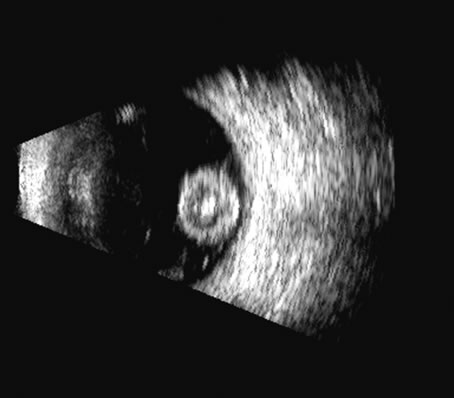

segment vitreoretinal disorders]. Yen Ko Hsueh Pao [Eye Science] 13:192, 1997 11. Coleman DJ: Evaluation of ciliary body detachment in hypotony. Retina 15:312, 1995 12. Coleman DJ, Wilcox LM: The choroid: Its function, evaluation, and surgical management. In: Symposium on Medical and Surgical Diseases of the Retina and Vitreous. Transactions

of the New Orleans Academy of Ophthalmology, pp 1–24. St. Louis, CV Mosby, 1983 13. Coleman DJ, Smith ME: Ultrasonic criteria for surgically salvageable pre-phthisical eyes. In White D, Lyons EA (eds): Ultrasound in Medicine, pp 297–298. Vol 4. Proceedings of the 22nd Annual Meeting of the American Institute of Ultrasound

in Medicine. New York, Plenum Press. 1978 14. Coleman DJ, Jack RL: B-scan ultrasonography in diagnosis and management of retinal detachments. Arch Ophthalmol 90:29, 1973 15. Bronson NR, Fisher YL, Pickering NC: Ophthalmic Contact B-Scan Ultrasonography for the Clinician. Westport, CT, International Publication, 1976 16. Downey DB, Nicolle DA, Levin MF, Fenster A: Three-dimensional ultrasound imaging of the eye. Eye 10:75, 1996 17. Coleman DJ, Daly SW, Atencio A, et al: Ultrasonic evaluation of the vitreous and retina. Semin Ophthalmol 13:210, 1998. 18. Wu G, Silverman RH, Coleman DJ, et al: In vivo thickness of human detached retina by ultrasonic signal processing. Graefes Arch Clin Exp Ophthalmol 227:21, 1989 19. Coleman DJ, Rondeau MJ: Diagnostic imaging of ocular and orbital trauma. In Shingleton BJ, Hersh PS, Kenyon KR (eds): Eye Trauma, pp 25–40. St. Louis, Mosby-Year Book, 1991 20. Clemens S, Kroll P, Rochels R: Ultrasonic findings after treatment of retinal detachment by intravitreal

silicone instillation. Am J Ophthalmol 98:369, 1984 21. Jannson F, Sundmark E: Determination of the velocity of ultrasound in ocular tissues at different